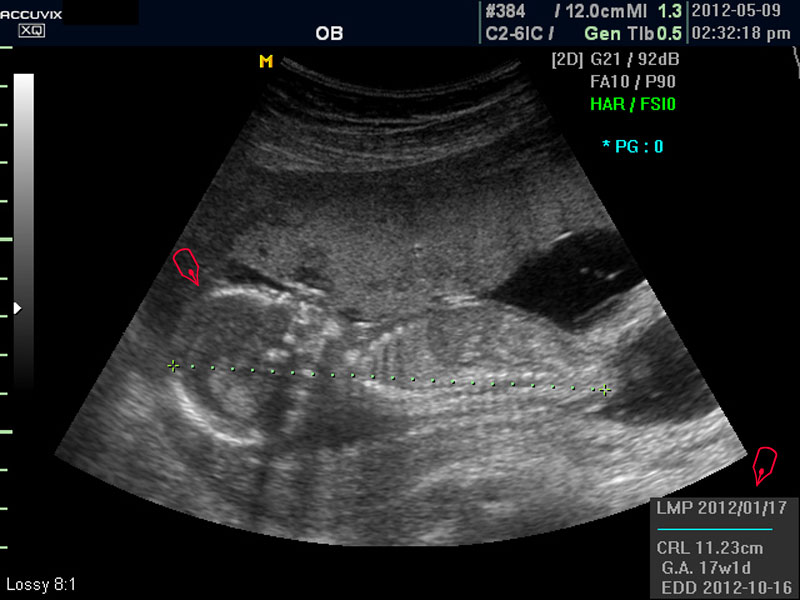

우선 초음파 사진에서 볼 것은 태아의 크기가 정상인가 하는 것입니다.

보통 태아의 발육은 머리부터 엉덩이까지의 크기인 CRL(Crown Rump Length의 약자)이 정상인가 하는 것과 태아의 두상 크기인 BPD(BiParietal Diameter의 약자)가 정상 범위에 들어 있는가 하는 것으로 판단합니다.

대신 첫번째 사진에서 보는 것처럼 태아의 전체 모습 특히 태아의 등쪽이나 복벽의 이상은 없는지 신경관 결손 등으로 인한 종괴가 있지는 않은지 관찰하며 태아의 복벽이나 등쪽은 일직선으로 매끈하게 보이는 것이 정상입니다.

첫번째 사진에서는 하지 부분은 대퇴부만 일부 보이며 이는 태아가 다리를 구부리고 있고 팔도 이리저리 움직여 머리 위나 목 쪽으로 두는 경우가 많아서 한번에 전체 모습을 찍기가 어려운 경우가 많습니다.

모든 사진에서 우측 하단에는 기본적인 발육 정보가 기록되는데 세번째 사진에서 빨간 펜으로 표시한 부분이며 그 내용의 의미는 아래와 같습니다.

참고로 이런 측정 수치가 나타나는 양식이나 위치는 초음파 장비마다 다르지만 용어는 대체로 공통된 의학 용어를 사용하기 때문에 대동소이합니다.

1. LMP

Last Menstrual Period의 약자로 최종 월경일입니다. 이런 최종 월경일을 바탕으로 현재의 임신 주수와 초음파상 측정 지표들간에 얼마나 괴리 되어 있나 하는 것을 판단하는 것입니다.

2. CRL

위에 말한 태아 크기를 말하는 지표로 실제 수치가 표시됩니다.

3. GA

Gestational Age의 약자로 우리말로는 임신 주기라고 하며 CRL이나 BPD등을 기준으로 했을때 임신 몇주 며칠에 해당하는 지 나타낸 것입니다.

5.EDD

Estimated Due Date의 약자로 초음파 측정치를 바탕으로 산출한 출산 예정일입니다.